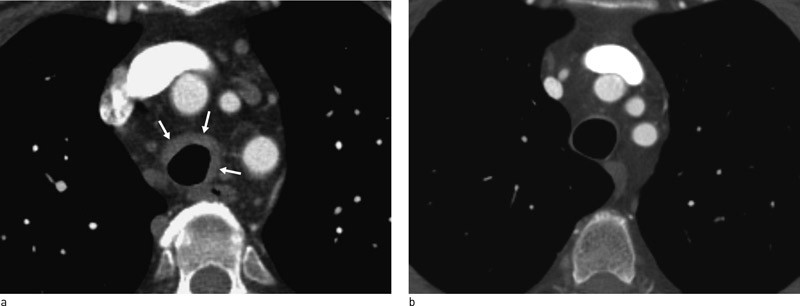

To måneder senere viste CT-undersøkelse av thorax patologiske funn. Det ble påvist veggfortykkelse oppimot 5 mm både i trachea og begge hovedbronkiene samt tydelig avsmalet lumen i hele forløpet til begge hovedbronkiene (fig 1). Denne gangen ble det også tatt bilder i ekspirasjon, som viste kollaps av hovedbronkiene til 4 mm (fig 2). Radiolog mistenkte trakeomalasi og anbefalte utredning med bronkoskopi. Påfølgende bronkoskopi viste tydelige tegn til kollapstendens i sentrale luftveier, mest uttalt i området rundt karina og venstre bronkialtre. Overflatisk bronkialbiopsi viste regelmessig slimhinne og noe arraktig fibrose, men uten bruskvev i prøvematerialet.

CT thorax er svært nyttig for vurdering av affeksjon av store luftveier. Typiske funn er veggfortykkelse og lumeninnsnevring i tra-chea, larynx eller bronkier og/eller ekspiratorisk kollapstendens i trachea og store bronkier (fig 1, fig 2). For å påvise kollapstendens i store luftveier er det helt avgjørende å ta tilleggsbilder i ekspirasjon, som hos denne pasienten, da vanlig CT i inspirasjon kan være helt normal. Selv om trakeomalasi er et karakterisk funn ved residiverende polykondritt, kan det ikke regnes for å være patognomonisk, da slike funn også kan forekomme ved Wegeners granulomatose og annen kronisk betennelse i luftveiene. Histologisk bekreftet diagnose med påvisning av kondritt i form av perikondrale lymfocyttinfiltrater er ønskelig (3). I praksis viser det seg dog ofte vanskelig å få dype nok biopsier med tilstrekkelig bruskmateriale.